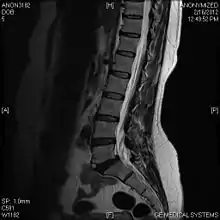

Viewed in a lateral radiograph, it appears as a triangular shaped bone fragment, not unlike an anterior lip fracture, but with softer edges.